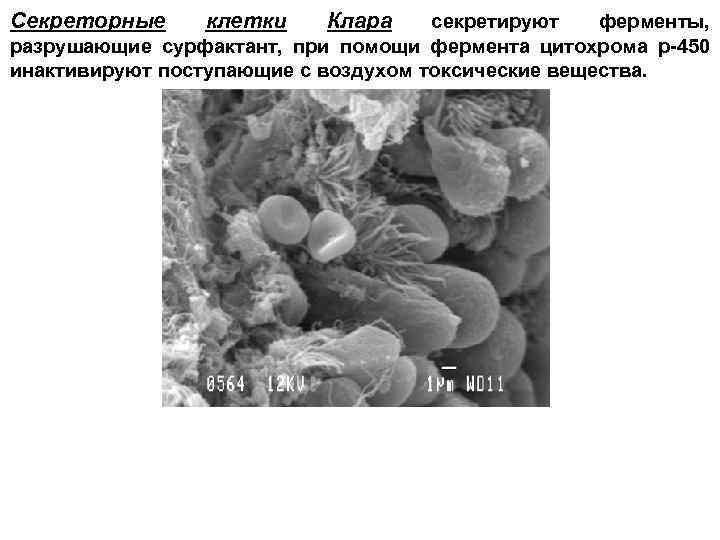

Секреторные клетки Клара секретируют ферменты, разрушающие сурфактант, при помощи фермента цитохрома р-450 инактивируют поступающие с воздухом токсические вещества.